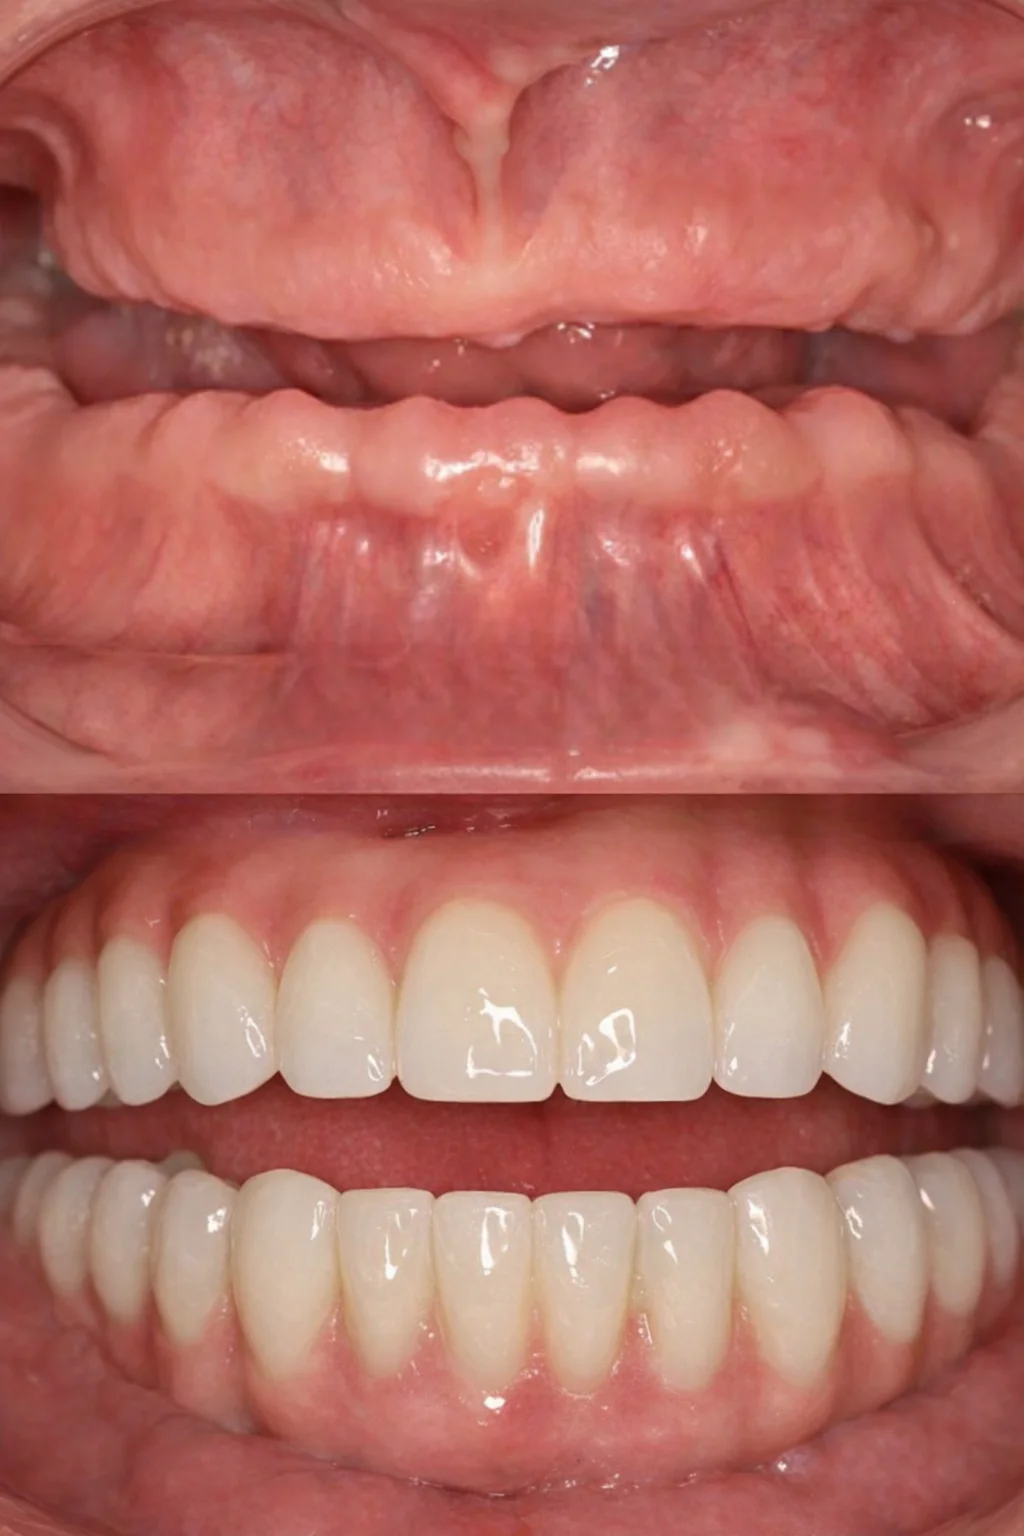

Долгое время пациентка стеснялась улыбаться и избегала фотографий из-за проблем с зубами и неудобных съёмных конструкций. Она откладывала лечение, считая, что восстановление будет долгим и тяжёлым. Отсутствие зубов на верхней и нижней челюсти требовало надёжного и долгосрочного решения.

На консультации мы подробно обсудили все варианты и выбрали современное и комфортное решение. Было выполнено полное восстановление зубных рядов по концепции All-on-6 с немедленной нагрузкой. В день операции установлены имплантаты и несъёмные протезы.

Сегодня пациентка улыбается уверенно, свободно общается и возвращается к привычной активной жизни без прежних ограничений.

Долгие годы жил без полноценного зубного ряда из-за страха большой операции. На консультации всё очень подробно рассказали и убедили, что процесс будет комфортным и не вызовет неприятных эмоций.

Провели реабилитацию верхней и нижней челюсти по концепции All-on-4 с немедленной нагрузкой. В день операции установлены имплантаты и несъёмные протезы.

Теперь точно все страхи позади. Пациент улыбается уверенно и ест без ограничений.